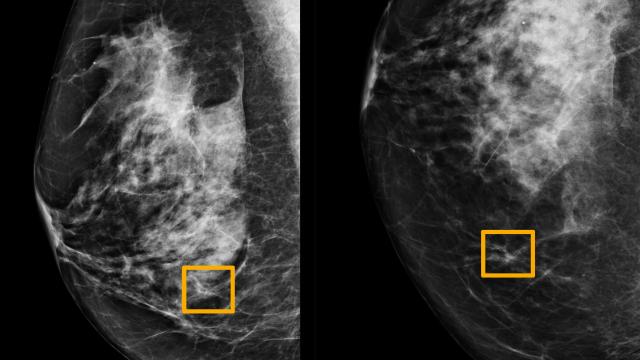

Cáncer de mama